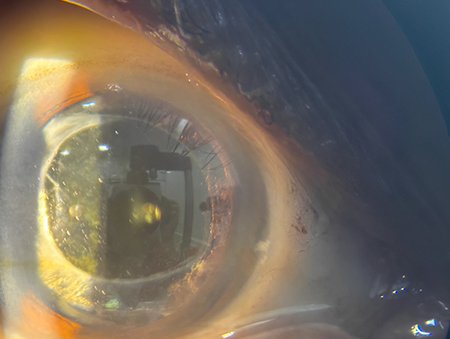

Chalazion – Successful Surgical Management At Vivaan ENT & Eye Clinic, we regularly manage eyelid conditions such as chalazion with safe, effective, and minimally invasive procedures. Recently, a patient underwent chalazion incision and curettage, performed by Dr. Veena Karkhele (Garje) under local anesthesia. The procedure was completed smoothly, and the patient had an excellent post-operative recovery with significant relief from swelling and discomfort.